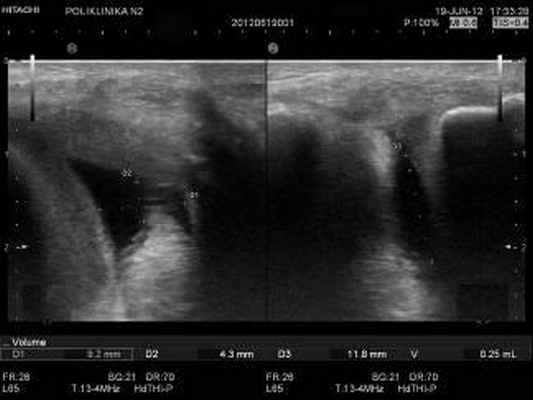

Частота локализации выпота в различных отделах коленного сустава и околосуставных сумках изолированно или в различных комбинациях изучалась на примере второй группы пациентов, состоящей из 308 пациентов с воспалительными заболеваниями коленного сустава. Данная группа состояла из 167 женщин и 141 мужчин в возрастной категории от 28 лет до 72 лет. Вычисления объема выпота проводились путем измерения трех сторон выпота в двух взаимноперпендикулярных плоскостях сканирования с применением функции « volume ».

Исследования проводились на аппаратах экспертного класса Hi Vision AVIUS (Hitachi) линейными датчиками с частотами 5-10 и 6-14 МГц и MINDRAY DС-7/М7 линейным датчиком L12-4 с частотой 3.0-13МГц.

В таблице 1 представлены результаты измерений толщины синовиальной оболочки в различных отделах коленного сустава 108 пациентов с длительностью течения воспалительного процесса в суставе не более 1,5 месяца. Градация толщины синовиальной оболочки в таблице составлена на основе трех степеней воспалительного процесса: незначительного, умеренного и выраженного. Воспалительные изменения синовиальной оболочки выражались в виде отклонений от нормативных значений в сторону увеличения толщины синовиальной оболочки. В результате полученных данных выявлено, что при воспалительном процессе коленного сустава степень изменений толщины синовиальной оболочки не равномерна в различных отделах одного и того же коленного сустава. Из таблицы видно, что максимальные значения толщины синовиальной оболочки определяются в супрапателлярной сумке (рис. 5). Меньшие значения толщины синовиальной оболочки определяются в латеральном подсвязочном пространстве коленного сустава (рис. 3,4). В центральной части полости коленного сустава изменения толщины синовиальной оболочки значительно менее выражены по сравнению с двумя предыдущими отделами (рис. 2). При различных степенях выраженности воспалительного процесса, основанной на клинических проявлениях, неравномерность изменений толщины синовиальной оболочки в различных отделах коленного сустава сохраняется c различной степенью выраженности изменений синовиальной оболочки. В данном случае выраженность воспалительного процесса в суставе влияет на степень изменения толщины синовиальной оболочки в различных отделах сустава. Например, при незначительном воспалительном процессе в коленном суставе толщина синовиальной оболочки, выстилающей полость супрапателлярной сумки, изменяется до 4 мм , синовиальная оболочка латерального подсвязочного пространства реагирует незначительно, а синовиальная оболочка центральной части сустава может иметь нормативные значения. При выраженном воспалительном процессе прослеживается та же последовательность выраженности изменений толщины синовиальной оболочки в изучаемых отделах. При выраженном воспалительном процессе толщина синовиальной оболочки супрапателлярной сумки более 6 мм , толщина синовиальной оболочки латерального подсвязочного пространства от 4 мм до 6 мм , толщина синовиальной оболочки центральной части сустава до 4 мм . Это доказывает неравномерность изменений толщины синовиальной оболочки в различных отделах сустава при различной степени выраженности воспалительного процесса. При ультразвуковом определении степени выраженности воспалительного процесса в суставе, основанном на изменениях синовиальной оболочки , нужно учитывать изменения синовиальной оболочки во всех отделах коленного сустава.